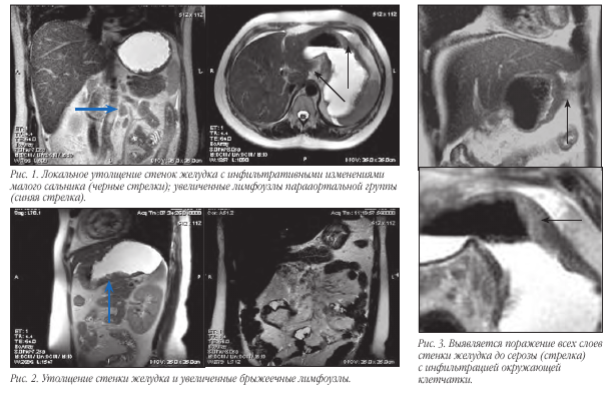

В связи с тем, что визуализировать достоверно все слои стенки желудка чаще всего не представляется возможным, то критериями ее поражения являются степень утолщения и протяженности изменений. При поражении всех слоев и распространении процесса за пределы серозы основными МР-признаками следует считать нечеткость и размытость наружного контура стенки желудка, снижение сигнала от перигастральной жировой клетчатки. В современной лучевой диагностике МРТ применяется для определения стадии по N и M стадиям, используя TNM классификацию. Мы в своей работе используем классификацию Японской ассоциации по раку желудка. В основе классификации JGCA (1998) лежит анатомический принцип. В отличие от принципов JGCA, классификация UICC (Международного противоракового Союза 2002) рассматривает лишь количественное поражение регионарных лимфатических узлов вне зависимости от их локализации.

Глубина опухолевой инвазии записывается, используя Т-классификацию. Анатомический уровень инвазии стенки желудка указывается следующим образом:

Т1: опухоль поражает слизистый слой и/ или подслизистый слои.

Т2: опухоль поражает собственно слизистый или субсерозный слой.

Т3: опухоль пенетрирует серозный слой.

Т4: опухоль инвазирует окружающие ткани.

Метастатическое поражение лимфоузлов, печени и брюшины - N, H и P.Основными признаками поражения стенок желудка являются: утолщение стенки более 5 мм, неровность и бугристость контуров, изменение МР-сигнала от образования, распространение за пределы стенки.